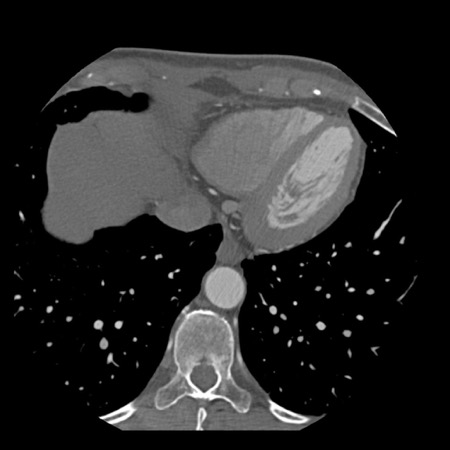

case 4 – CAD-RADS 3/P1/I+ thrombus left ventricle

First, scroll through the CTA images.

How would you describe the findings on the coronary CTA?

The findings are:

- Moderate (50-69%)

stenosis in the proximal LAD caused by a non-calcified plaque. - Variant of

sinoatrial (SA) nodal artery. The artery usually arises from the RCA as a second

branch after the conus artery, however in this case it arises from the LCX,

courses behind the aorta, anastomosing with the right atrium and with a small

branch supplies the SA-node of the heart. - Thrombus in the

apex of the left ventricle. - CTP was performed

in this patient. CTP showed a perfusion defect at stress imaging in the

territory of the LAD (I+), at rest no perfusion defect was visible.

This patient classifies as CAD-RADS 3/P1/I+, which means

this patient requires further investigation.